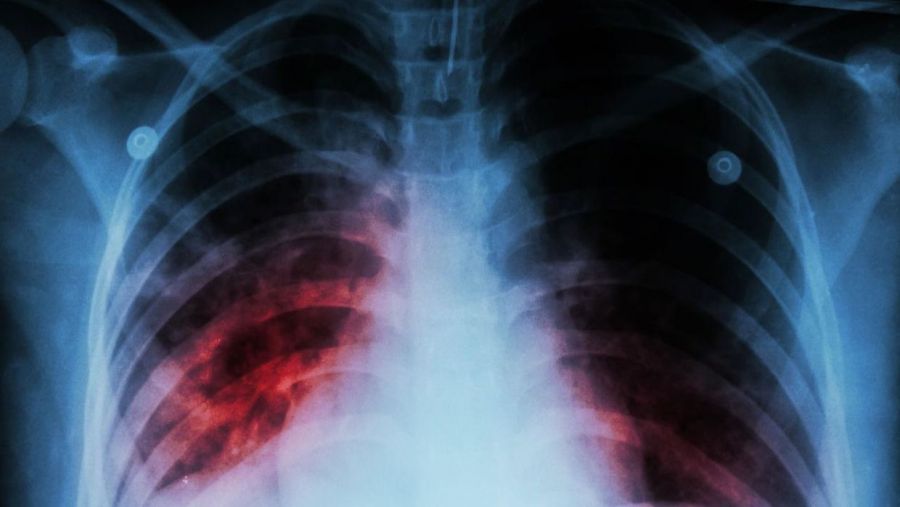

Explicó que la Fibrosis Pulmonar Idiopática se caracteriza por un proceso anormal y desconocido que favorece la cicatrización del intersticio pulmonar que hace que se vuelva rígido y vaya reduciendo su tamaño. A medida que avanza la cicatrización del tejido pulmonar, el paso del oxígeno al torrente sanguíneo a través de los pulmones se hace cada vez más difícil. Esto ocasiona dificultad para respirar y que los órganos no reciban suficiente oxígeno para funcionar con normalidad.

Por eso, ante cualquier sospecha de signos y síntomas es importante que los afectados acudan con un médico neumólogo, quien a través de una serie de estudios diagnósticos podrá determinar su presencia. “Si bien el diagnóstico es complicado, más del 80% de los pacientes con FPI tienen un sonido distintivo tipo velcro (crepitación) que puede detectarse por medio de un estetoscopio[ix]. Y, una vez detectada la FPI, se debe iniciar tratamiento inmediato”, agregó la Dra. Buendía.